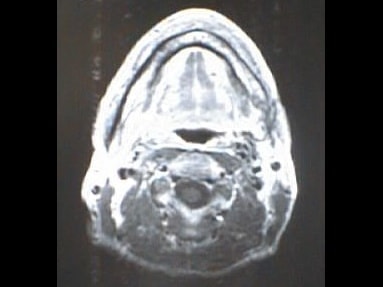

MRI画像比較

入院当時MRI画像②

入院3か月後癌消滅MRI画像②